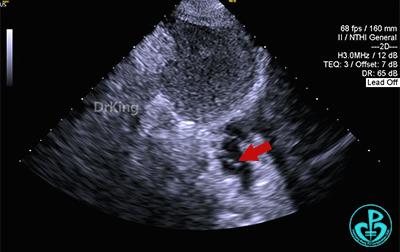

房间隔中部有回声中断,测ASD大小:8×8×9mm,CDFI探及左向右分流,距主动脉根部0mm,距二尖瓣环10mm,距房顶14mm,距上腔静脉13mm,距下腔静脉11mm。

心脏彩超提示:先天性心脏病:房间隔缺(继发孔型)。右室稍增大。左心室收缩及舒张功能正常。右心室收缩功能正常。下腔静脉瓣冗长。